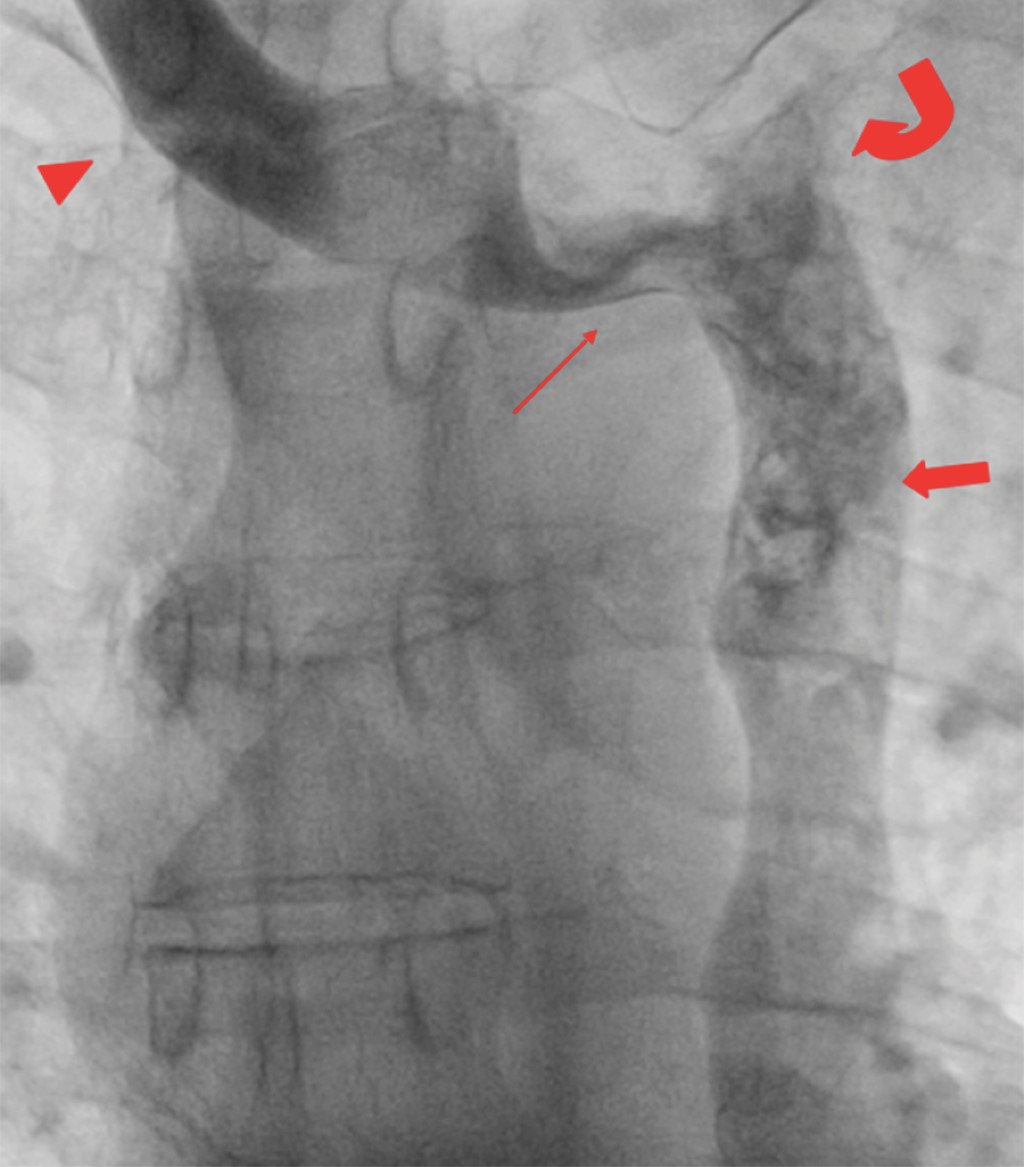

Pacemaker implantation through the persistent left superior vena cava due to the absence of the right superior vena cava. Report of a case

Introduction: the persistence of the left superior vena cava (PLSVC) has a prevalence of 0.21% in the general population. Case presentation: 67-year-old male diagnosed with third-degree AV block, requiring pacemaker placement. However, due to the absence of a right superior vena cava, corroborated by CT angiography, a definitive pacemaker was placed through a persistent left superior vena cava. Conclusion: the persistence of the left superior vena cava (PLSVC) is the most common thoracic venous anomaly. It can cause a number of clinically significant symptoms, even in a heart with normal anatomy. Pacemaker placement makes electrode fixation difficult due to tortuous travel.

Figure 2